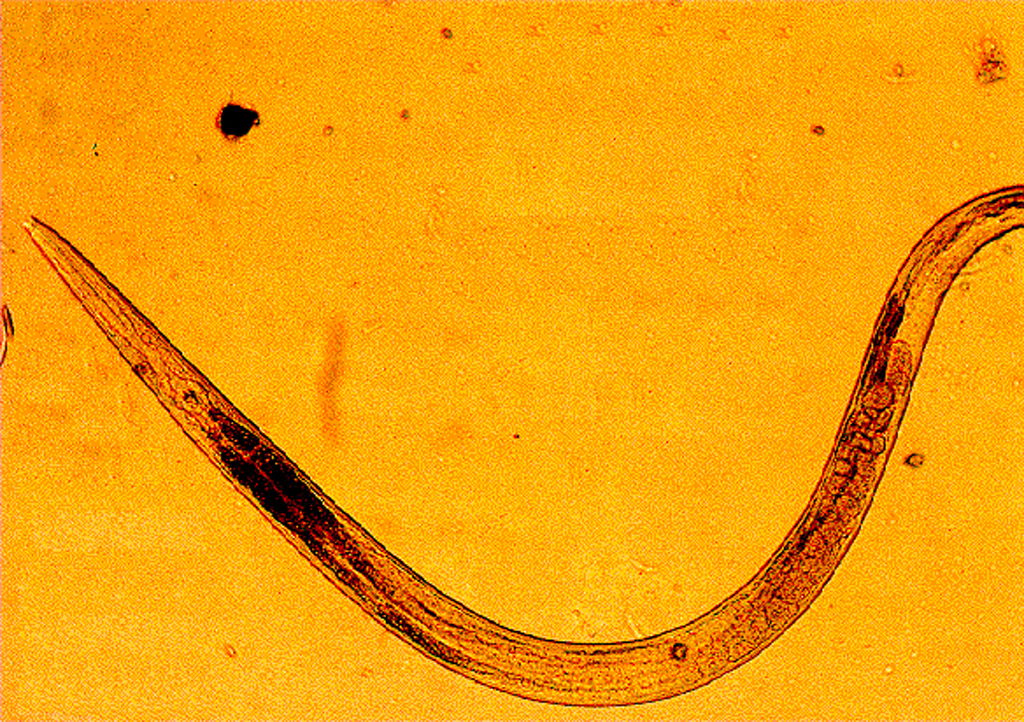

Over a billion of mostly third world people are infected with a roundworm known as ascarids. Ascarids are tiny parasites that infect the intestinal tract of vertebrates. Movement of the larvae into the brain or other parts of the body can prove fatal. Space-based research is providing new hope in combating these parasitic worms. Ascarids are dependent upon a substance known as malic enzyme to regulate certain bodily functions. A new drug designed to interfere with normal functioning of malic enzyme should prove deadly to ascarids. The Center for Macromolecular Crystallography, along with the University of North Texas grew malic enzyme crystals on the USML-1 Spacelab mission. Although these crystals proved to be smaller than ground based ones, they were more perfectly formed, therefore producing better data for drug design.